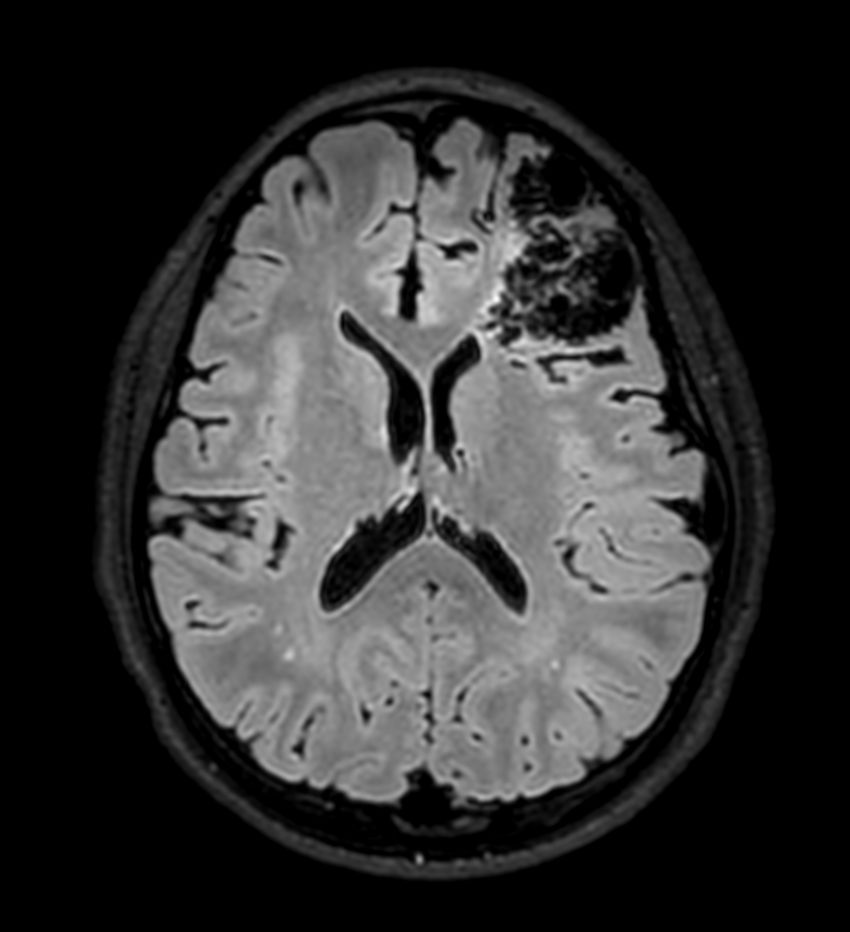

Pediatric brain with AVM

Pediatric patient with frontal brain AVM. MultiVane XD is used to achieve high resolution diagnostic images, even in the case of severe patient motion. SWIp sequence is added to acquire exquisite susceptibility contrast. The 3D sequences with isotropic voxel size enable reformats in any plane without loss of resolution. And 4D-TRAK XD, a fast, dynamic contrast-enhanced MR Angiography method allows to achieve high spatial and temporal resolution simultaneously. Integration of Compressed SENSE acceleration technique enables speeding up of the entire exam.

Axial SWIpCompressed SENSE